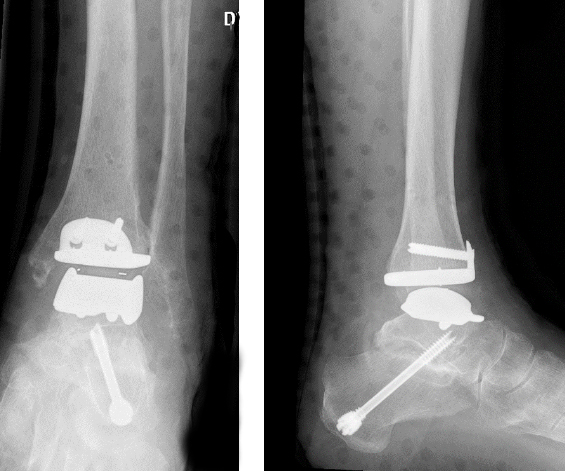

Endoprothese (Kunstgelenk) des oberen Sprunggelenkes

Das obere Sprunggelenk hat beim normalen Gangablauf eine sehr wichtige Funktion. Es ermöglicht die Bewegung des Fußes nach "oben" und "unten". Bei Abnützungen dieses Gelenkes wird dieser Bewegungsablauf stark gestört. Dies macht sich v.a. in Form von einer sehr schmerzhaften Bewegungseinschränkung bemerkbar. Bis vor wenigen Jahren war die einzige Therapieform die Versteifung dieses Gelenkes. Die wesentlich modernere und funktionell günstigere Versorgung stellt allerdings die Implantation eines Kunstgelenkes dar.

Dies stellt die modernste Technik und zweifelsohne anspruchsvollste Versorgung einer symptomatischen Arthrose des oberen Sprunggelenkes dar. In seiner Tätigkeit als leitender Oberarzt des Kinder-, Fuß- und Sprunggelenkteams der Univ-Klinik für Orthopädie in Innsbruck hat Dr. Gerhard Kaufmann bei über 70 Patient/Innen ein solches Gelenk implantiert. Die Endoprothese des oberen Sprunggelenkes kann aber nur gut funktionieren, wenn die gesamte Biomechanik und Funktion des Fußes berücksichtigt und eventuell mitkorrigiert wird. In ca 50% der Fälle ist somit vor, während oder nach der Implantation einer Endoprothese ein zusätzlicher Eingriff am Fuß, sowohl knöchern mittels Korrekturosteotmien als auch mittels Versteifungen sowie weichteilig mittels Sehnentransfers notwendig.

Die Nachbehandlung erfolgt mittels Schiene oder Gips bis die Wunde verheilt ist. Danach wird mit dem Belastungsaufbau und der Bewegungstherapie des Kunstgelenkes begonnen. Nach ca 6 Wochen sollte die Vollbelastung möglich sein und ein annähernd normaler Bewegungsumfang des oberen Sprunggelenkes erreicht werden. Somit ist diese Versorgung des oberen Sprunggelenkes eine Technik, die eine normale Funktion des gesamten Fußes ermöglicht.

Nachteil dieser Technik ist die aller Kunstgelenke, nämlich, daß Kunstgelenke einem Verschleiß unterliegen, der nach ca 10 Jahren Folgeoperationen notwendig macht.